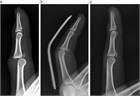

1. 指が物にぶつかって受傷するいわゆる「突き指」には、骨折や靭帯損傷など重度の損傷が隠れている場合がある。

1. 注意深い診察とX線写真撮影により、損傷に応じた適切な治療を行うことが推奨される。